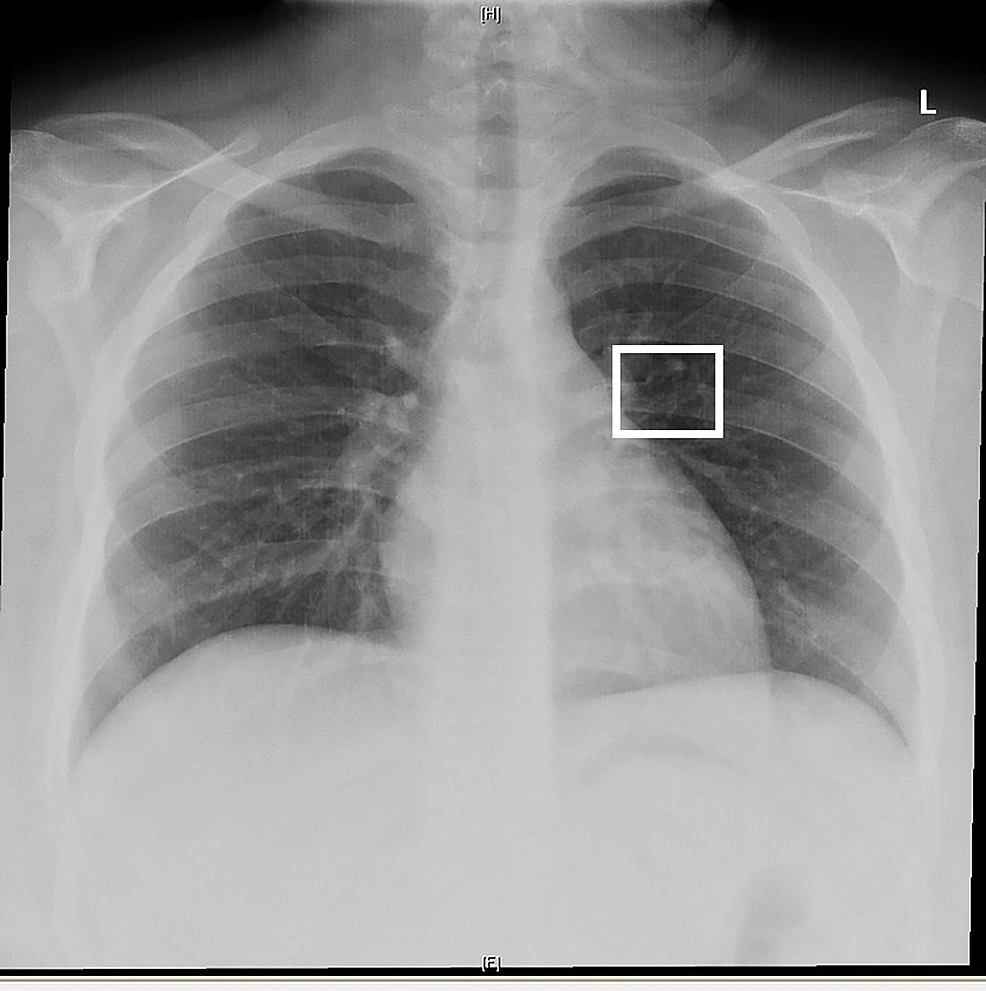

Indications for chest x ray in pneumonia picture This image demonstrates Indications for chest x ray in pneumonia.

Information technology also discusses the quality, usability, and size of the available datasets, and. The publication of this study and photo chart could act. The current covid-19 epidemic threatens human animation, health, and productivity. It is for free burning use but behind be stopped and restarted at some point. Left-sided injury is more common with left-to-right ratio 3:1. Chest x-ray results influenced diagnosis by the general practitioner fashionable 53% of cases and patient direction changed following X ray in 69% of patients.